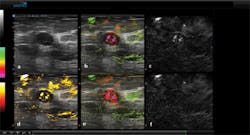

This post-processing, as well as image segmentation tasks such as thresholding, were performed using an embedded GPU from NVIDIA (Santa Clara, CA, USA; www.nvidia.com) programmed in CUDA. Results of this processing are then transmitted through the DVI port of the host PC and displayed on a 23-in medical grade 1920 x 1200 In-Plane Switching (IPS) LCD monitor, with six images being displayed on the screen (Figure 3).

Figure 3: (a) A greyscale ultrasound image, (b) a combined ultrasound and opto-acoustic image with oxygenated blood (green) and de-oxygenated hemoglobin (red), (c) data captured after tissue is subjected to reflected 757nm laser light shows deoxygenated hemoglobin, (d) a segmented opto-acoustic total hemoglobin image with total hemoglobin displayed in yellow, (e) a non-segmented, opto-acoustic image with oxygenated blood in green and relatively de-oxygenated blood in red, and (f) reflected 1064nm laser light shows oxygenated blood.

In this panel of images, abnormal cells have been found in the lining of the breast milk duct and the areas that produce milk (lobules). While Figure 3a shows a standard greyscale ultrasound image, Figure 3b displays a combined ultrasound and opto-acoustic map. This is pseudo-colored to show relatively oxygenated blood as green and relatively de-oxygenated blood as red and has been thresholded to minimize the colorization of the surrounding tissues.

To show the relatively more de-oxygenated hemoglobin, Figure 3c displays the results of data captured after the tissue is subjected to 757nm laser light while Figure 3f is the result of data captured after being subjected to the 1064nm laser light and shows more relatively oxygenated blood. Finally, Figure 3d shows a segmented opto-acoustic total haemoglobin image with total hemoglobin displayed in yellow while Figure 3e is a non-segmented opto-acoustic image that shows oxygenated blood in green and relatively de-oxygenated blood in red and is not subjected to a threshold. Segmentation lines manually drawn on the ultrasound image were used to co-register locations on the five opto-acoustic images to highlight the opto-acoustic results.

While the greyscale ultrasound image can identify the morphological features of the tissue, the relative degree of oxygenation or de-oxygenation of the vessels representing functional information can be seen in both the overlaid ultrasound and opto-acoustic images as well as the opto-acoustic images alone.